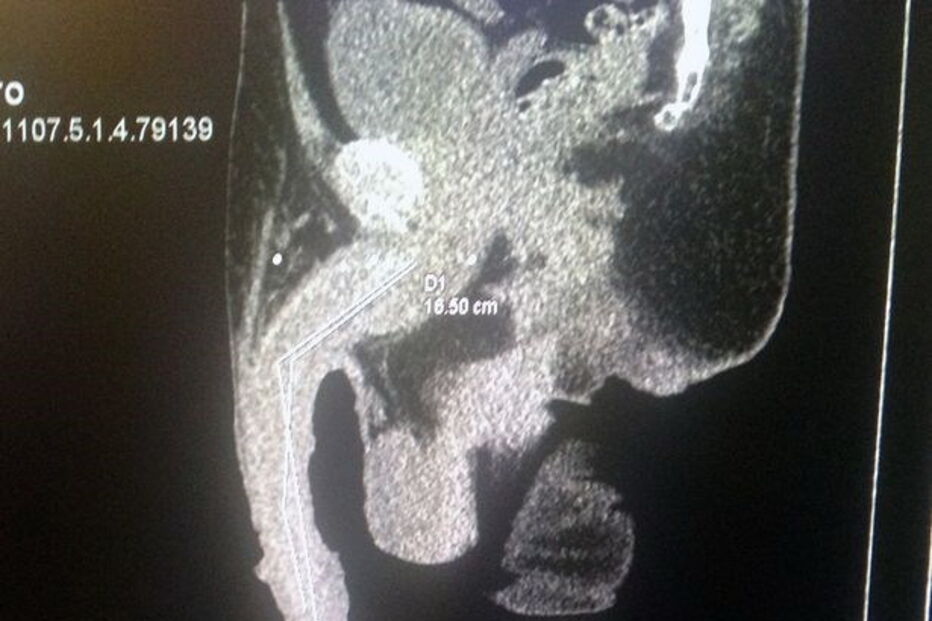

Roberto deu que falar em todo o mundo devido aos 48 centímetros da sua 'masculinidade' e ao facto de querer entrar para Livro de Recordes do Guinness.